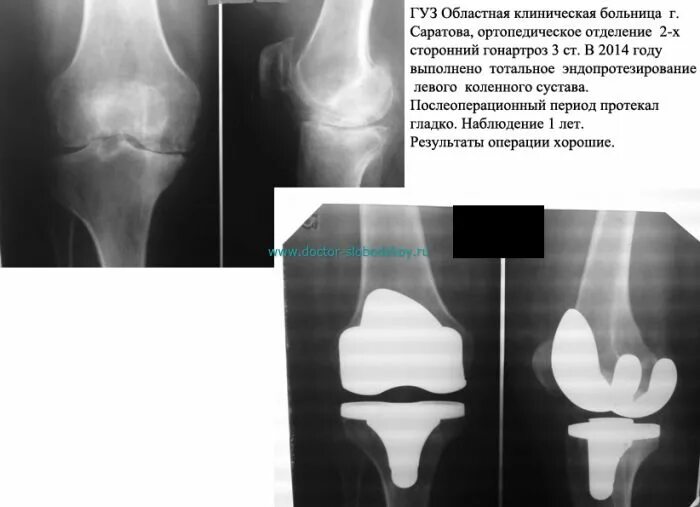

Можно ли эндопротезом делать мрт